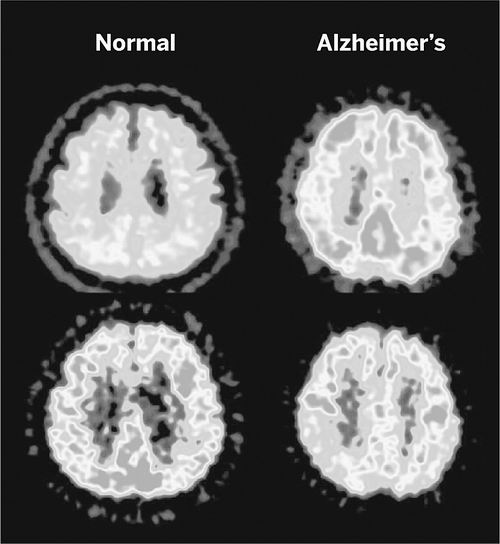

J-ADNI项目使用扫描技术对比正常人(左)和阿尔茨海默氏症患者的大脑

还有另一个问题。一份同样发布于6月24日的东京大学独立报告称,他们没有发现,阿尔茨海默氏症神经影像学创新计划(J-ADNI)存在日本媒体所说的数据篡改行为。但该报告称,J-ADNI项目管理“毫无经验”,数据处理也应受指责。

J-ADNI负责人、东京大学神经病学家Takeshi Iwatsubo表示,该项目耗资3100万美元、涉及38家机构的努力,在规模和复杂性方面,对日本而言是“史无前例的”。他也承认该项目在寻找有经验的数据管理者和生物统计学家方面遇到了麻烦,从而导致了一个坎坷开端。